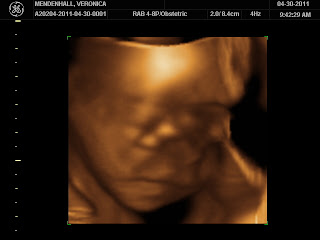

Oh and of course I can't forget to leave you with a picture of baby M from our 3D ultrasound

Best moment this week: We had 3D ultrasound done,

so getting to see parts of his face was awesome!

(I say parts because someone was cooperating)